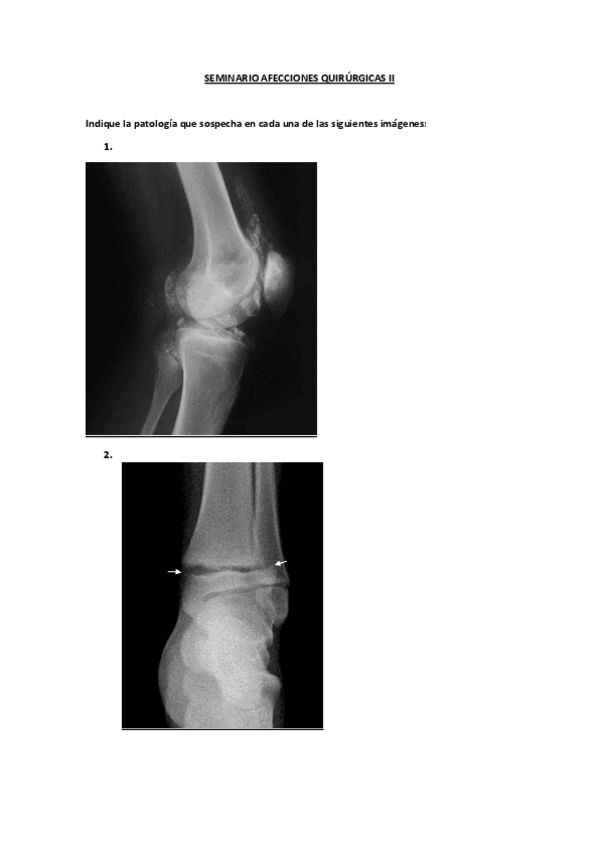

SEMINARIOS BEA

He publicado nuevos trabajos de 2º Afecciones Quirúrgicas: SEMINARIOS BEA

SEMINARIO-AFECCIONES-QUIRURGICAS-II.pdf